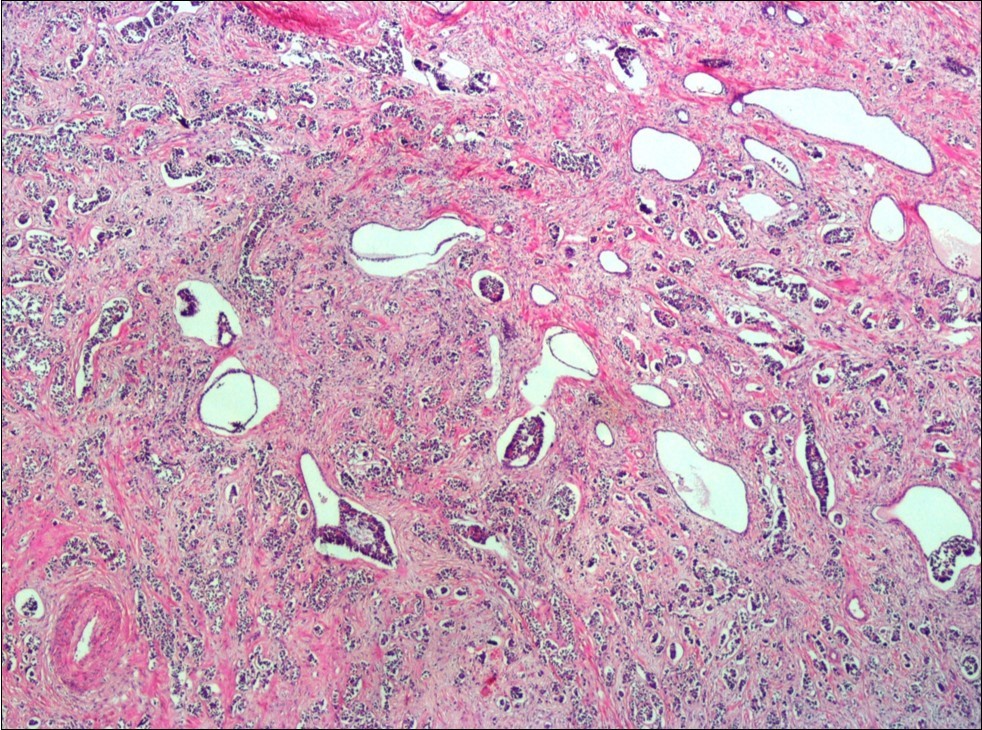

A 73-year-old male patient was admitted to our outpatient clinic with acute urinary retention. Digital rectal examination was normal. The PSA value was 1.81 ng/dl. Prostate size was 101 cc. Since the PSA value and digital rectal examination were normal, no biopsy was taken. Ultrasonography showed bilaterally ureterohydronephrosis. The creatinine level was 2.89 mg/dl. Hypertension has been presented as a comorbidity. An 18 Fr Foley catheter was inserted and alpha-blockers and 5-α reductase inhibitor medication was given. Creatinine level decreased to 0.91 mg/dl after one week. When the patient's catheter was pulled out, he could not urinate again. A catheter was inserted and waited one week more. After one week, the patient was unable to urinate again. The operation was decided due to this recurrent urinary retention. Because of prostate size was 101 cc and prostatic urethra was long, open prostatectomy was decided. When the prostate was removed during the operation, it was evaluated that the left side and the lower side were adhered to surrounding tissue. The prostate was removed as an en bloc. The catheter was removed after 5 days. The pathology of the patient has been reported as pure small cell prostate carcinoma. On the microscopic examination, the tumor was heavily infiltrated into the prostate parenchyma (Figure 1). Tumor cells were consist of atypical small-medium sized, mitotically active cells with a high nuclear to cytoplasmic ratio, hyperchromatic nucleus, nuclear molding, and inconspicuous nucleoli (Figure 2). On the immunohistochemically examination of synaptophysin showed diffusely and strong positivity while chromogranin A showed focal weak positivity with the absence of staining for PSA (Figure 3). Ki67 proliferative index was equal to 90% of the tumor cells (Figure 4). The results confirmed the diagnosis of prostatic small cell carcinoma. Metastatic lymph nodes were detected in the right perirectal region with metastatic multiple lymph nodes in the bilateral external iliac region, more on the left than in the PET CT. No metastasis was detected in the brain MRI and thorax computed tomography. Four cycles of etoposide and cisplatin chemotherapy were administered to the patient. Control PET CT taken after chemotherapy showed a significant decrease in size and metabolic activity of the right obturator and lymph nodes in the right perirectal area. The size and metabolic character of the left obturator, left external iliac and common iliac lymph nodes were increased. After a month, patient admitted to emergency outpatient clinic with left flank pain. There was an 8-cm mass in retroperitoneal area in the computed tomography. Supportive treatment was started because the patient could not tolerate chemotherapy. The masses reached to 13x11cm and fulfilled the retroperitoneal area. Multiple lung metastases were seen. The patient died 13 months later after the first diagnosis.

Figure 2.The tumor cells show rosette formation with hyperchromatic nuclei and nuclear molding (H&E, x200)